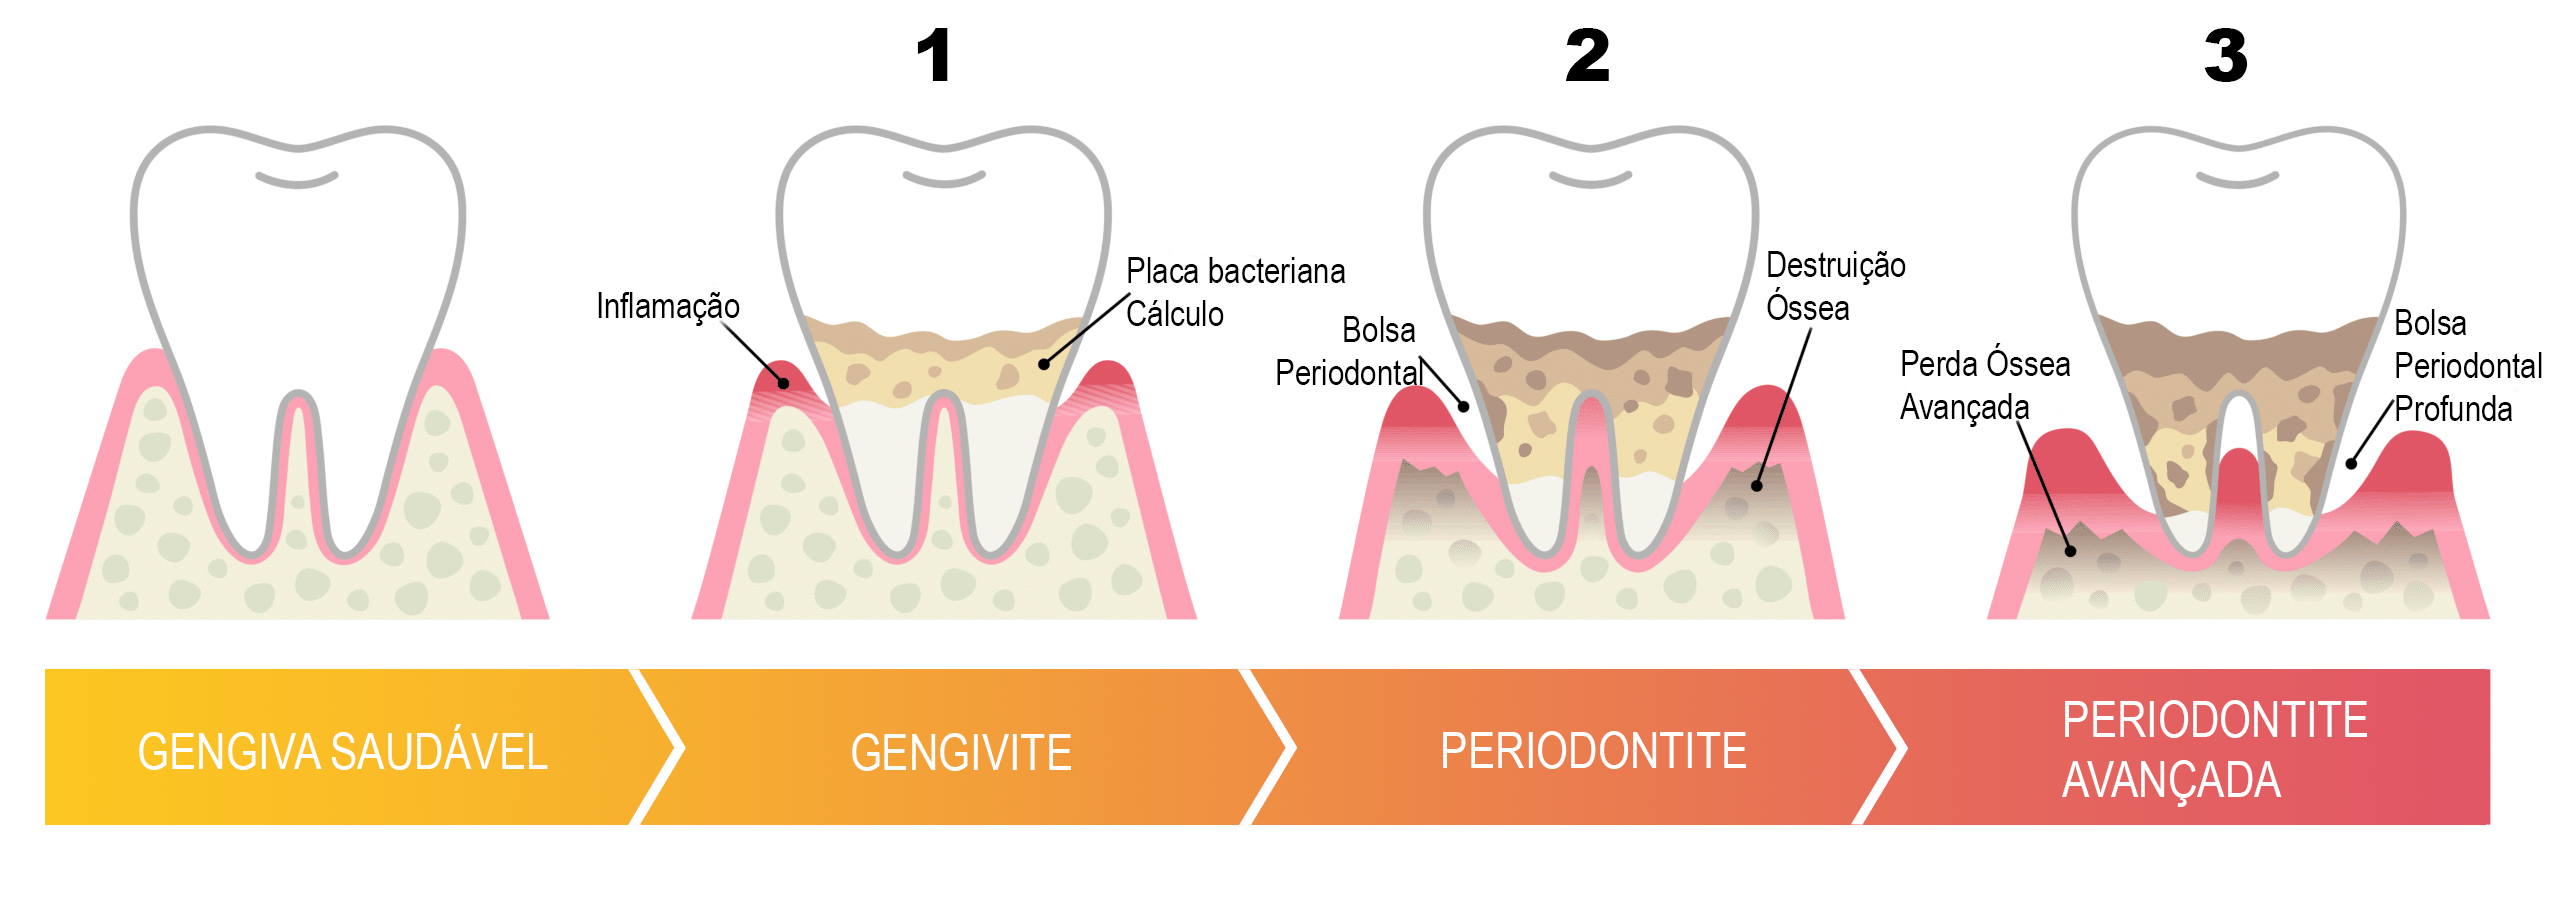

Quase tudo começa na gengivite — inflamação inicial e reversível. Sem tratar, vira periodontite, que destrói o osso. Ache seu sintoma abaixo e toque para entender:

Da gengiva saudável à periodontite: a doença avança em silêncio quando não é tratada.

← arraste para ver os 4 estágios →

A forma avançada da doença: a inflamação passou da gengiva e chegou ao osso que segura o dente. O osso já perdido não volta — mas o avanço pode ser parado. E ela age em silêncio, sem dor. Toque em cada tópico:

O que é periodontite

A periodontite — a antiga "piorréia" — é o estágio avançado. A inflamação ultrapassou a gengiva e atingiu o ligamento e o osso. A bolsa aprofunda, bactérias proliferam embaixo da gengiva e o osso vai sendo destruído: lento, silencioso e irreversível. O tratamento controla a doença e impede o avanço — mas o osso já perdido raramente volta sem cirurgia. Por isso o diagnóstico precoce é tudo.